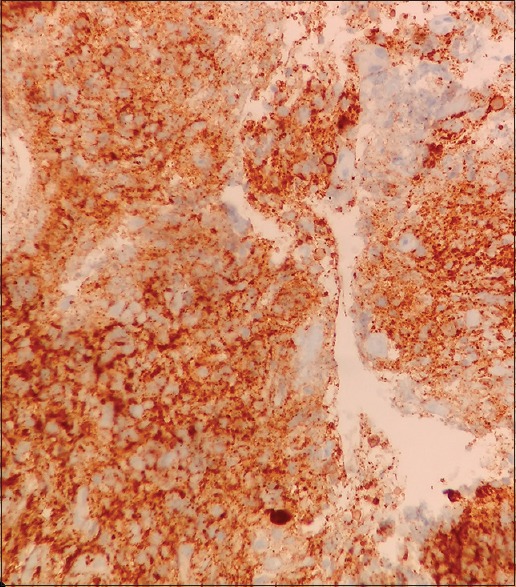

A 65-year-old female with no history of comorbidities was admitted to our hospital on July 5, 2014 with painless lump in her right breast. On detailed history taking, patient had no history of fever, night sweats, or weight loss (B symptoms). Physical examination revealed a hard, nontender, mobile mass of approximately 6 cm × 7 cm occupying all quadrants of the right breast. The contralateral breast was normal. On physical examination, patient had no evidence of cervical, axillary or inguinal lymphadenopathy. Liver and spleen were not palpable. The laboratory tests revealed the following: Hemoglobin of 11.9 g/dl, total leukocyte counts of 10,400/mm3, platelet counts of 48,600/mm3, serum creatinine of 0.72 mg/dl, alkaline phosphatase of 55 IU/L, serum glutamic pyruvic transaminase of 22 IU/L, serum glutamic oxaloacetic transaminase of 13 IU/L, total bilirubin levels of 0.88 mg/dl, serum albumin of 4.34 g/dl, lactate dehydrogenase (LDH) of 172 U/L, and serum uric acid of 4.52 mg/dl. Excisional biopsy performed showed atypical lymphocytic infiltration suspicious of non-Hodgkin's lymphoma (NHL) [Figure 1]. Immunohistochemistry revealed positivity to CD20 [Figure 2], CD79a and MUM1 and negativity to CD2, CD3, CD5, CD10, and AE1. MIB-1 index was 95%. On the basis of histopathologic features, tumor was classified as DLBCL, non-germinal centre B-cell-like (non-GCB DLBCL). Bone marrow aspiration and biopsy were performed and revealed a hypercellular bone marrow with no evidence of lymphomatous infiltration. The cerebrospinal fluid cytological examination was negative for any malignant cells. Computed tomography (CT) of the neck, thorax, abdomen, and pelvis revealed 66 mm × 68 mm × 84 mm large multi-lobulated soft tissue density lesion involving all quadrants of right breast reaching up to the skin [Figure 3]. No systemic lymphadenopathy was detected. The CT findings indicated stage I E of the lymphoma tumor according to the Ann Arbor staging system. The patient received six courses of cyclophosphamide, doxorubicin, vincristine, prednisolone plus rituximab (R-CHOP) chemotherapy. After four courses of R-CHOP, the follow-up chest CT scan showed decreased the size of the right breast mass (6.6 cm × 6.8 cm → 3.4 cm × 1.4 cm) [Figure 4]. After six courses of R-CHOP, the follow-up chest CT scan showed no visible mass in the breast. The patient was put under close observation. At present, after follow-up period of 20 months, the patient is surviving with no evidence of disease and with no morbidities associated with chemotherapy.

| Figure 4:Interim computed tomography scan done after four cycles of cyclophosphamide, doxorubicin, vincristine, prednisolone plus rituximab showing marked reduction in size of right breast mass from 6.6 cm × 6.8 cm to 3.4 cm × 1.4 cm